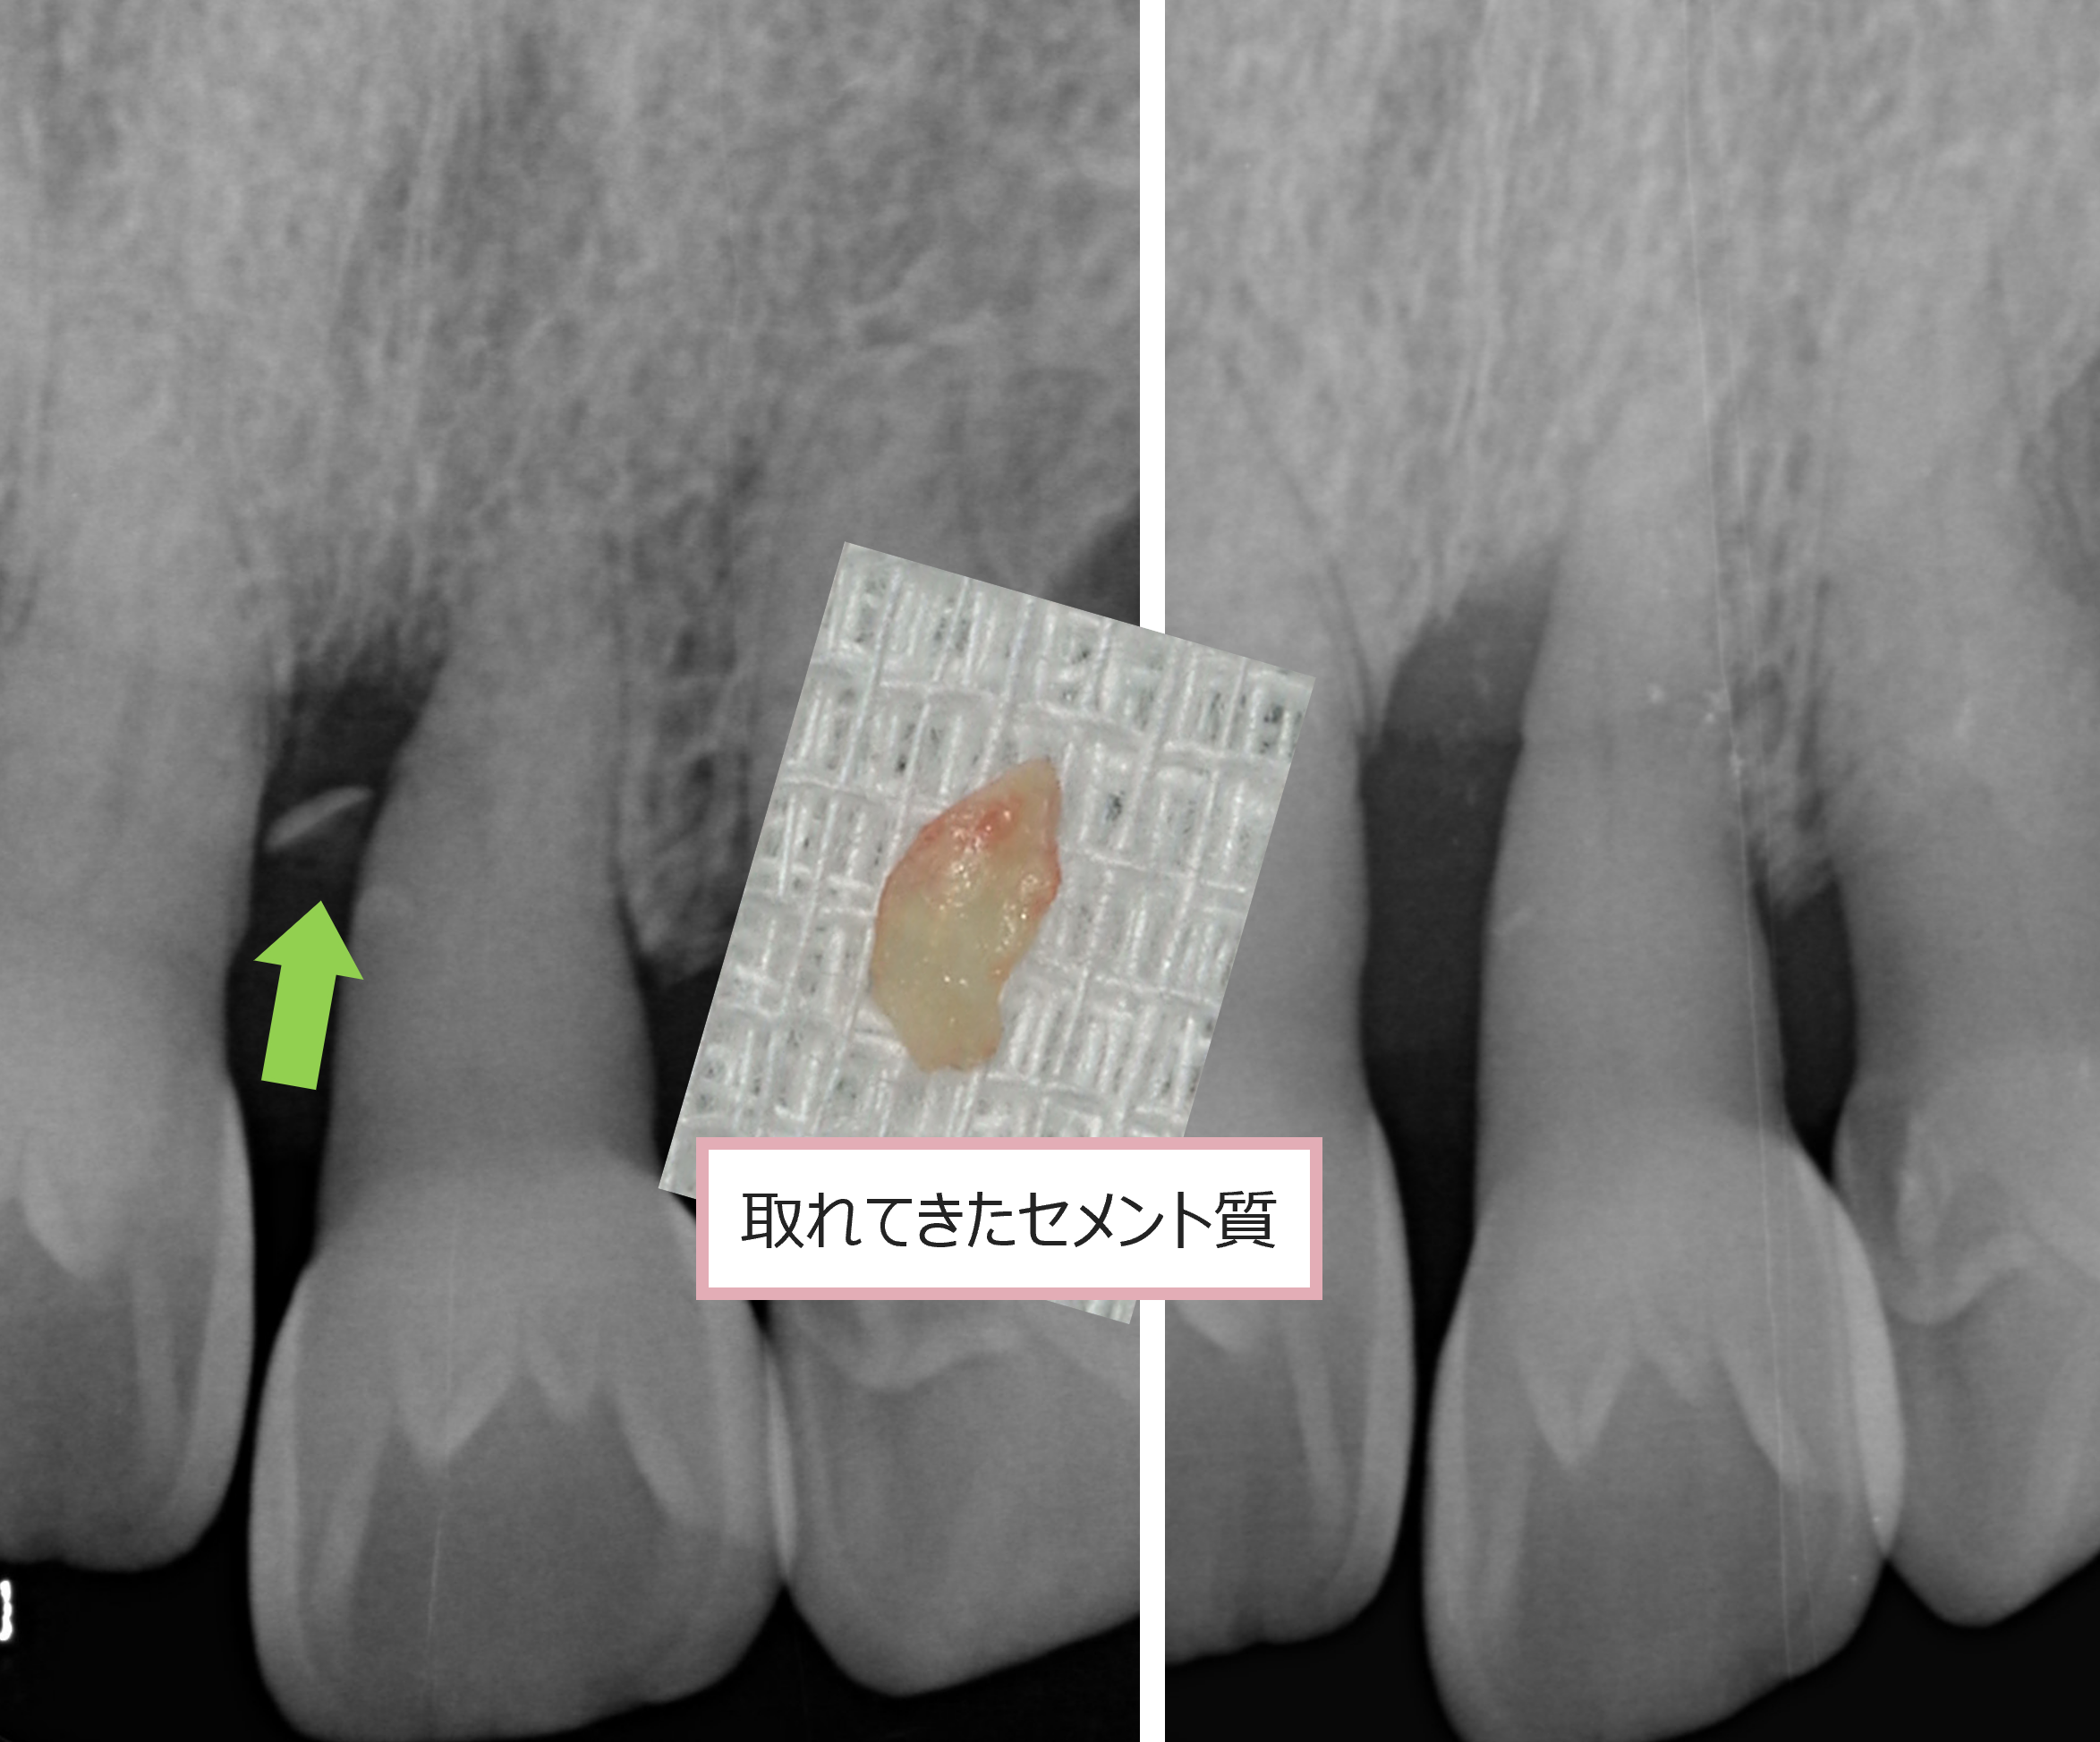

歯の根の部分には外側にセメント質という層があります。

これが歯を支える骨とつながっている大事な構造です。

そのセメント質が、突然歯の本体から剝がれることがあります。

それをセメント質剥離と呼びますが、

▼当院での症例